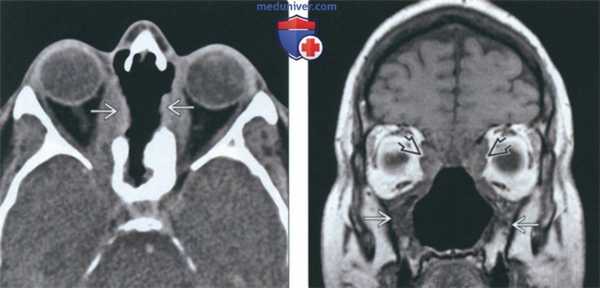

(Слева) При аксиальной «костной» КТ определяется узловой мягкотканный компонент, заполняющий полость носа; снижена пневматизация верхнечелюстных пазух. Носовая перегородка перфорирована, стенки пазух утолщены и склерозированы, что типично для ГПА.

(Справа) При аксиальной «костной» КТ в случае далеко зашедшего ГПА определяется тотальная центральная деструкция полостей носа, включая перегородку, раковины, наружные стенки. Верхнечелюстные пазухи блокированы утолщенной костью.

(Слева) При аксиальной КТ без КУ определяется деструкция верхней части носовой перегородки и глазничной пластинки с обеих сторон. В этом случае имеет место гранулематоз с распространением в обе орбиты.

(Справа) При корональной МРТ Т1ВИ у этого же пациента определяется нарушение нормальной анатомии носа и утолщение стенок верхнечелюстных пазух. Жировые пластинки между измененными мягкими тканями и внутренней прямой и верхней косой мышцами видны неотчетливо.